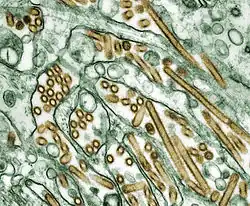

Influenzavirus A

Este género tem apenas uma espécie, o Influenzavirus A. As aves aquáticas selvagens são o hospedeiro natural de uma grande diversidade de vírus de gripe A. Ocasionalmente, estes vírus são transmitidos para outras espécies e podem dar origem a surtos devastadores em aves de criação ou desencadear pandemias de gripe humana.[35] Os vírus do tipo A correspondem aos patógenos mais virulentos entre os três tipos de vírus da gripe e estão na origem das formas mais graves da doença. Os vírus da gripe A podem ser divididos em diferentes serotipos em função da resposta dos anticorpos a estes vírus.[36] Os serotipos confirmados em seres humanos, ordenados pelo número de mortes em pandemias, são:

Gripe aviária

Os sintomas de gripe em aves podem variar e não ser específicos.[204] Uma infeção de gripe aviárias com baixa patogenicidade pode-se manifestar apenas através de plumagem baça, pequena redução na produção de ovos ou perda de peso, em conjunto com doença respiratória pouco intensa.[205] Uma vez que estes sintomas pouco graves dificultam o diagnóstico de campo, o rastreio de gripe aviária exige a análise em laboratório de amostras de aves infetadas. Algumas das estirpes, como a H9N2 asiática, são extremamente virulentas para as aves de criação e podem provocar sintomas mais graves e mortalidade significativa.[206] Na sua forma de maior patogenicidade, a gripe em galinhas e perus provoca o aparecimento súbito de sintomas graves e praticamente 100% de mortalidade em apenas dois dias.[207]

Uma estirpe extremamente patogénica de gripe aviária, denominada HPAI A(H5N1) e endémica em diversas populações de aves, sobretudo no sudeste asiático, está-se a disseminar à escala global. Uma vez que é epizoótica (epidémica em não humanos) e panzoótica (afeta animais de diversas espécies numa região de grande dimensão), é responsável pela morte de dezenas de milhões de aves selvagens e exige o abate de outras tantas de modo a controlar a sua disseminação. A maior parte das referências à "gripe aviária" e ao "H5N1" na comunicação social são relativas a esta estirpe específica.[208] Na atualidade, a estirpe HPAI A(H5N1) é uma doença aviária e não existem evidências que sugiram que seja transmitida de forma eficaz para o ser humano. Em praticamente todos os casos, os indivíduos infetados tinham tido contacto físico prolongado com as aves infetadas.[209] No futuro, é possível que o H5N1 possa sofrer mutação para uma estirpe capaz de contagiar de forma eficaz o ser humano, embora ainda não se conheçam as alterações exatas necessárias para que isto aconteça.[210] No entanto, devido à elevada mortalidade e virulência do H5N1, à sua presença endémica e ao cada vez maior número de hospedeiros, durante a época de gripe de 2006-2007 este vírus foi a principal ameaça de pandemia, tendo sido gastos milhares de milhões de dólares na preparação para uma avental pandemia.[189] Em março de 2013, o governo chinês divulgou três casos de infeções pela estirpe H7N9 em seres humanos. Em meados de abril, pelo menos 82 pessoas estavam já infetadas, das quais 17 viriam a morrer.[211]